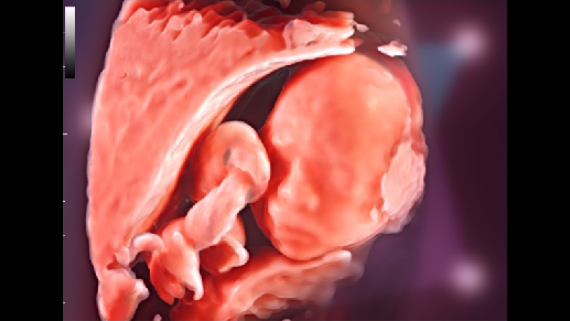

Imagens clĂnicas